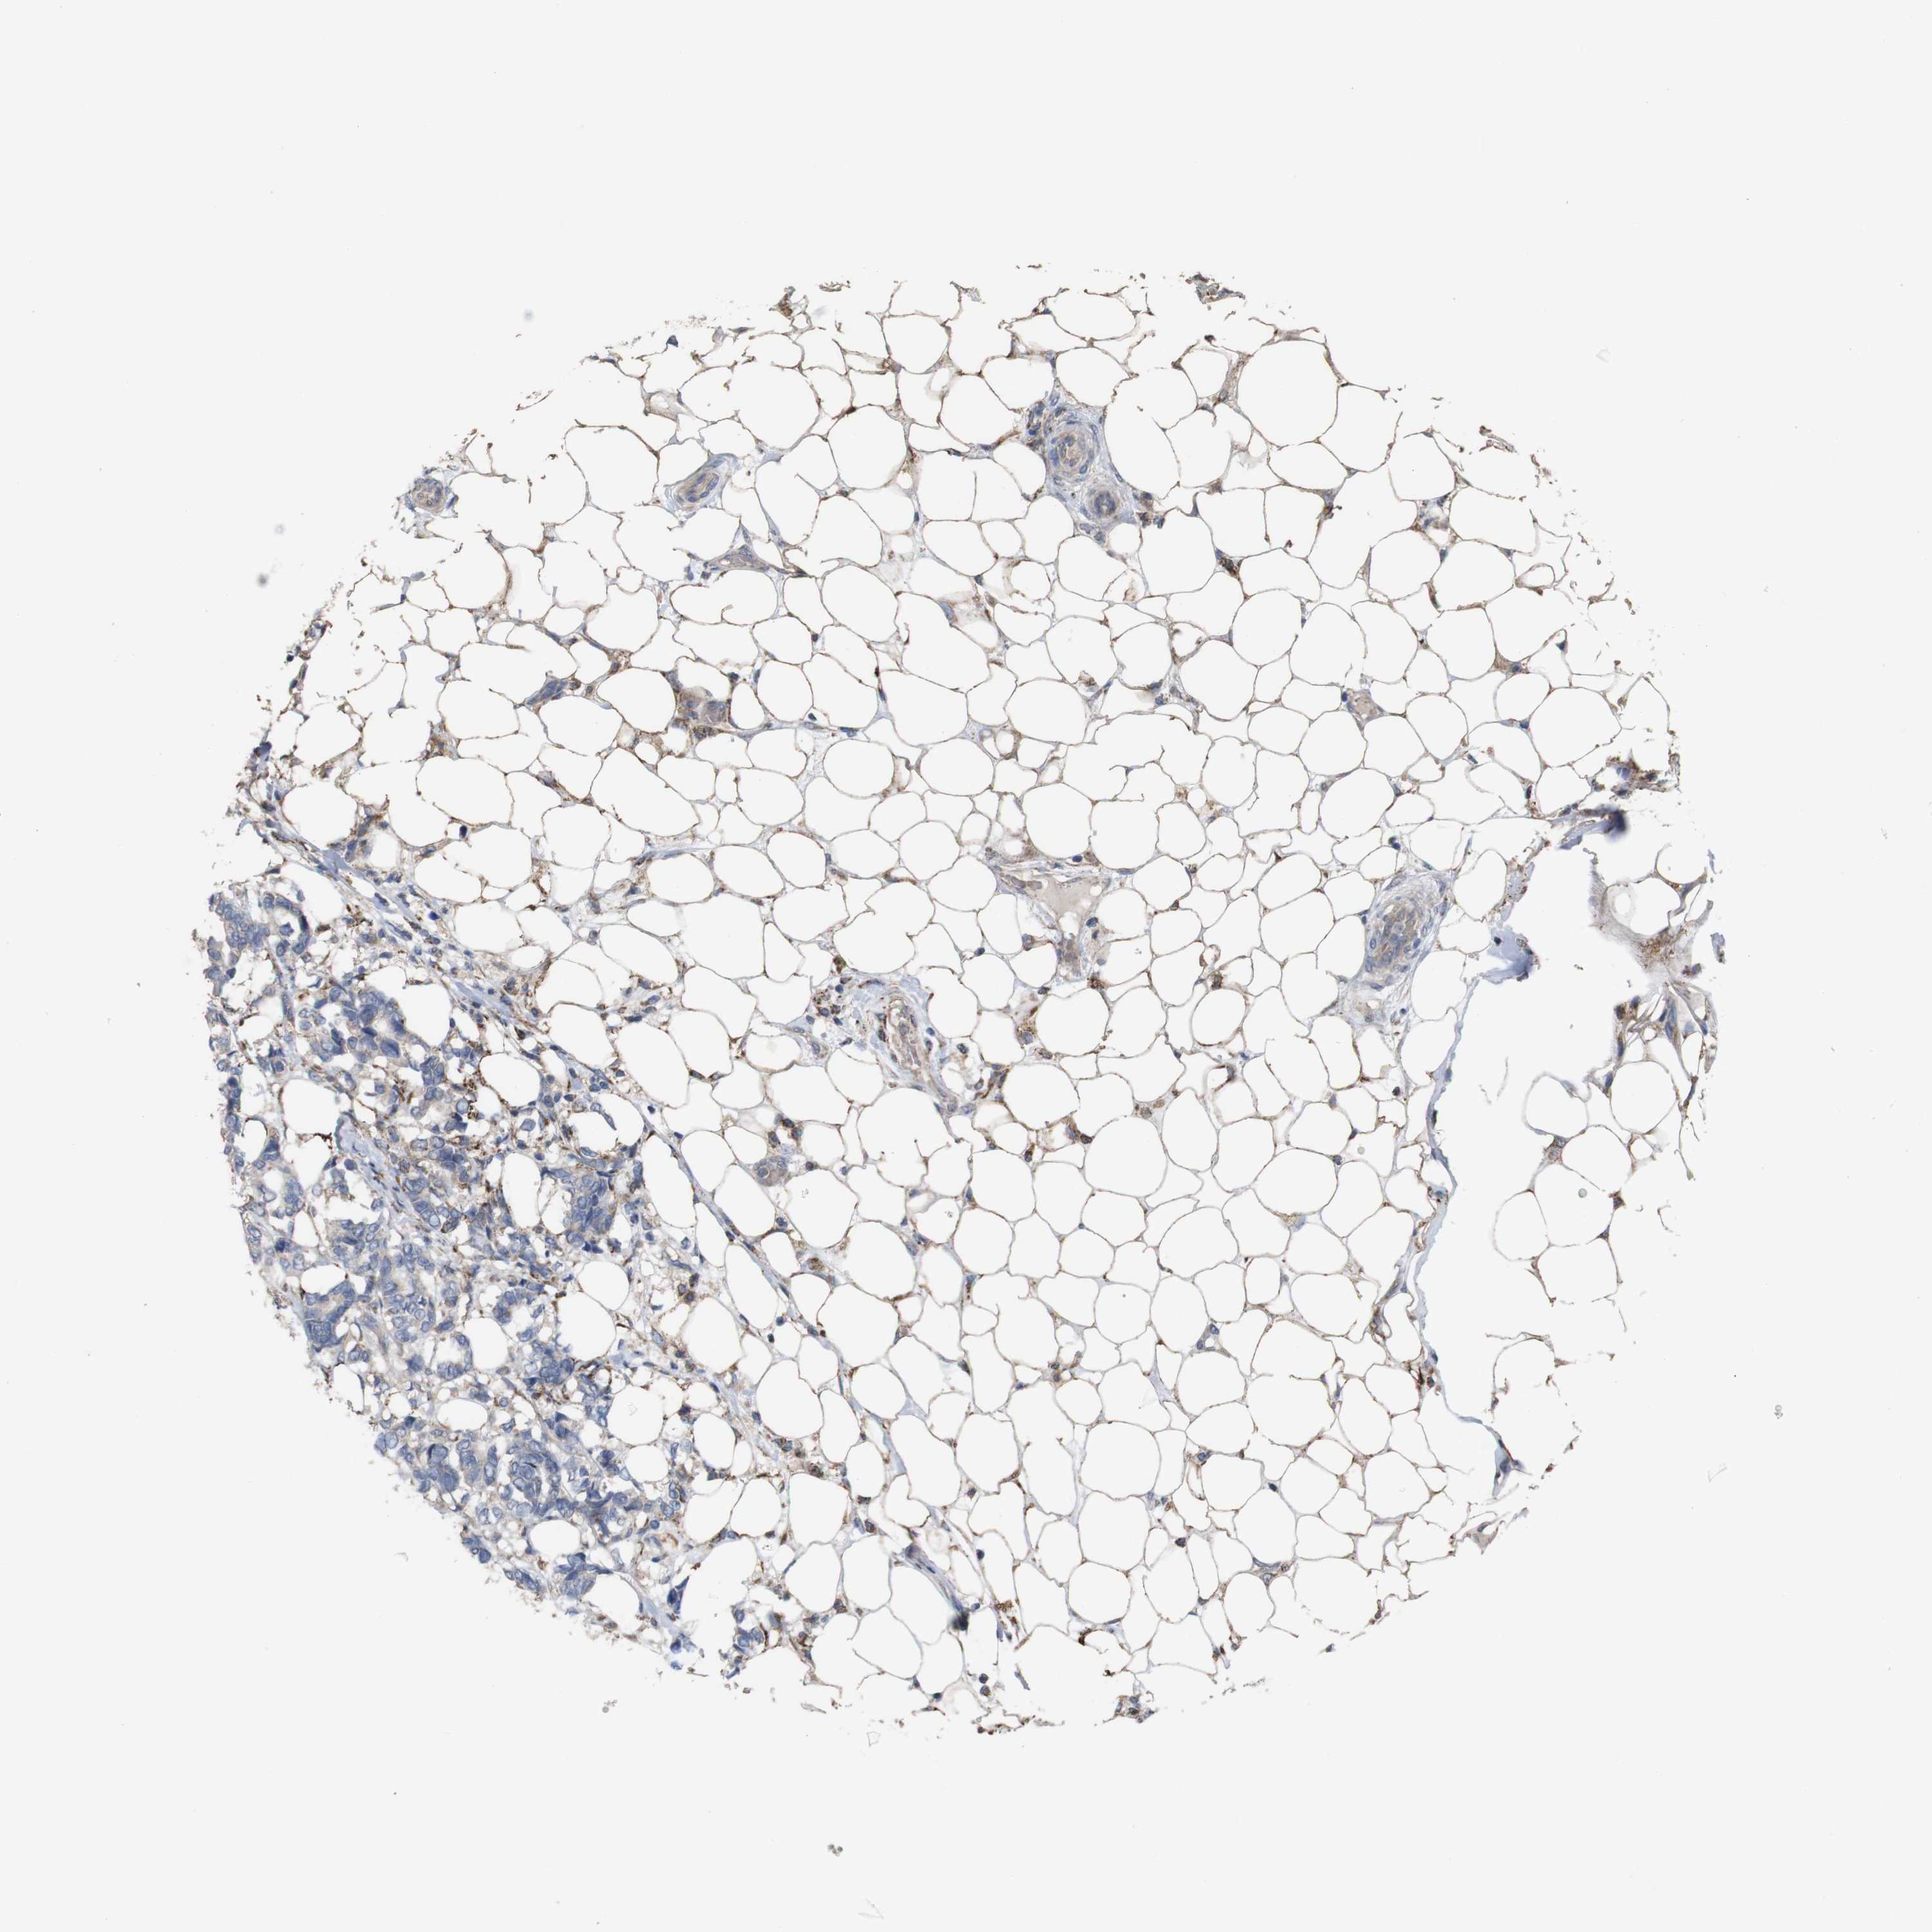

Breast cancer

Human cancer